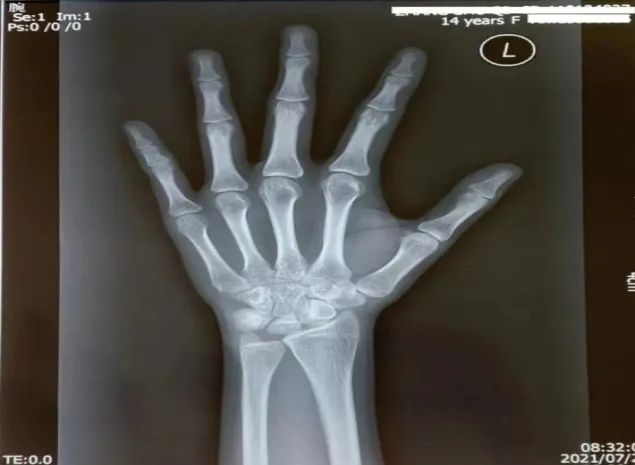

X线摄片检查主要用于一般的骨折及肺部检查。

X光检查具有时间短、费用低、检查方便的优点,但也存在人体结构会互相重叠,一些小的或特殊的病变可能会存在看不清的问题。